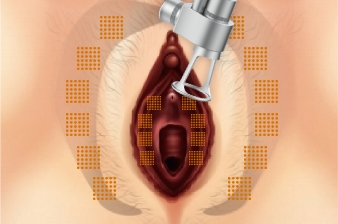

Treatment Procedure

Fractional Handpiece

01

Before the treatment Loosen vagina inner wall

02

03

04

05

06

07

Improve Vulva Discoloration